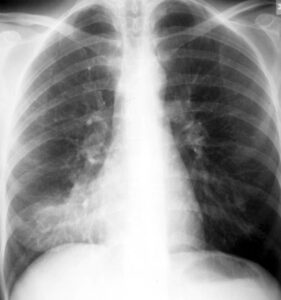

• Chest X-ray: To visualize the lungs and detect inflammation.